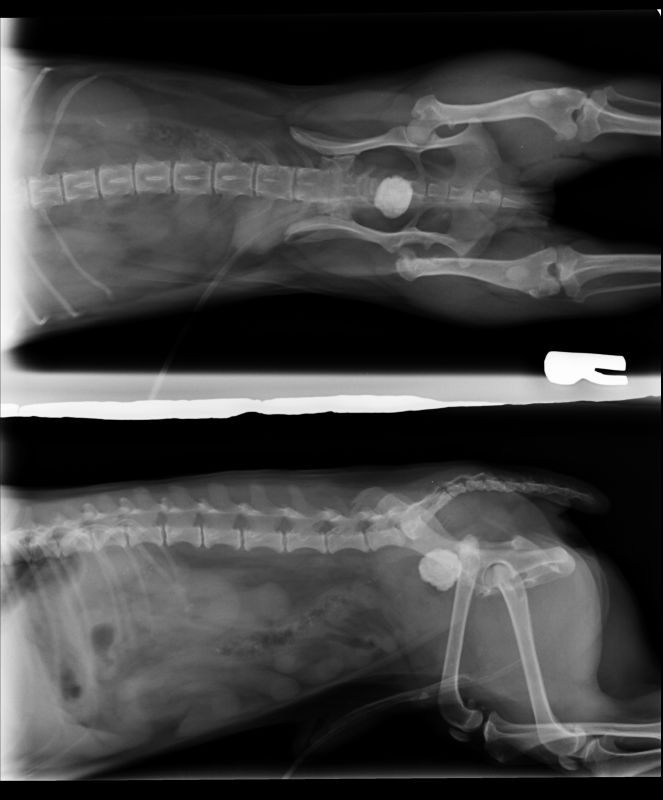

Abnormal Pathology on your pet

Shown on x-ray images which we have taken over the years.

Some interesting patient cases